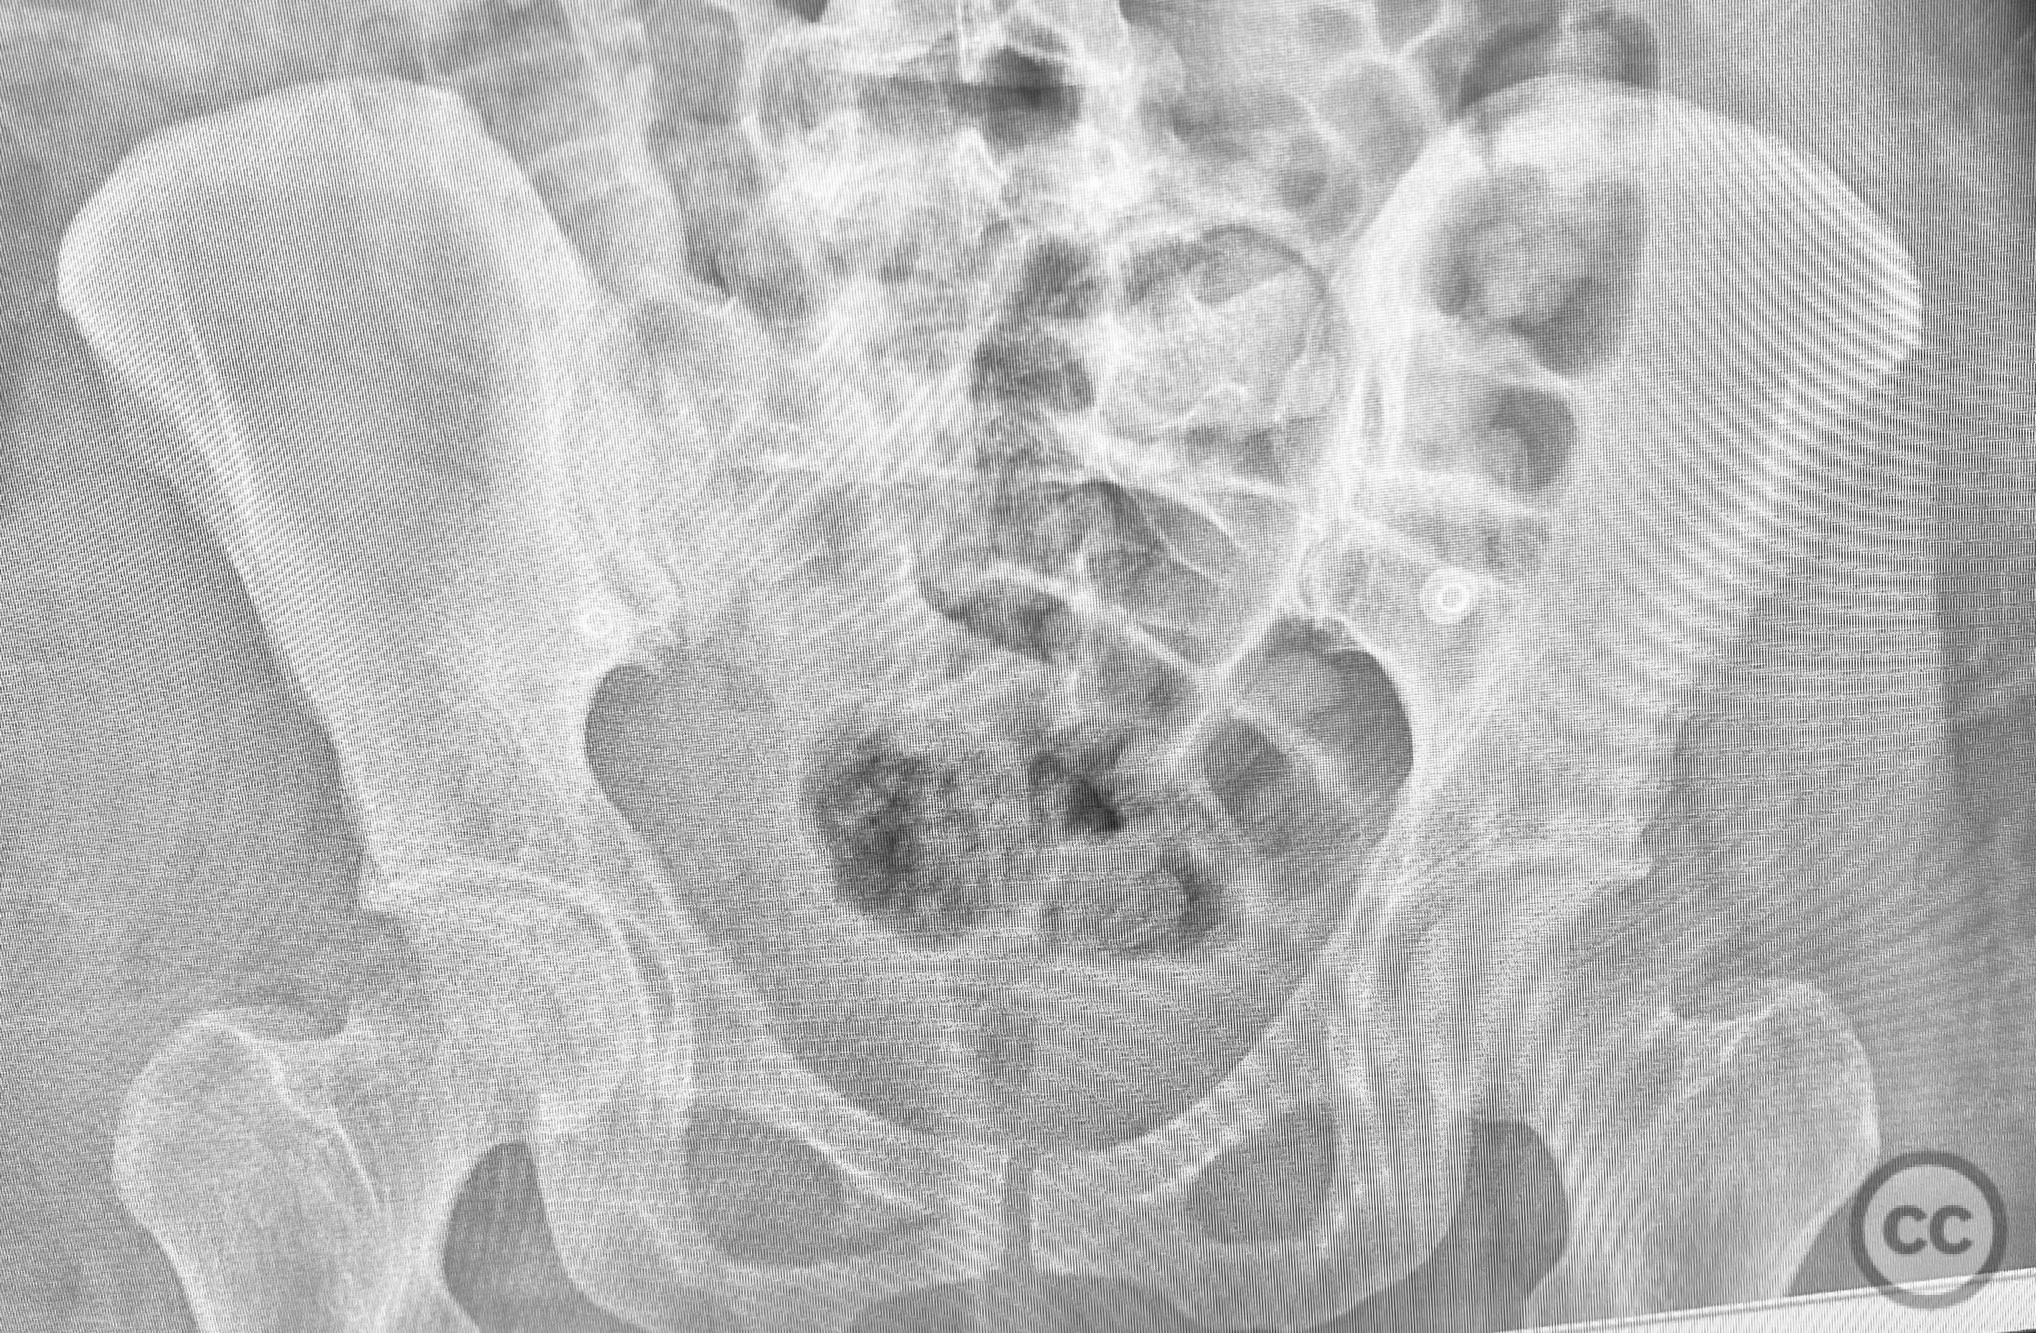

Pelvic Ring - AO/OTA 61x

Pelvis - AO/OTA 6x